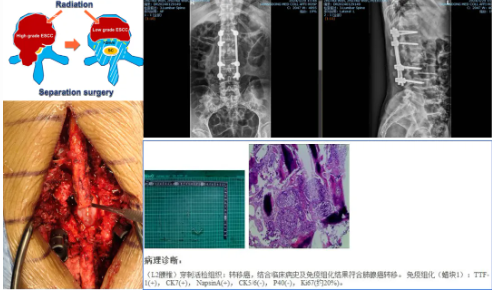

典型案例三

局麻下脊柱转移瘤射频消融手术联合椎体成形术

·患者凌某某,女,65岁,因反复腰背部疼痛半年余入院。腰背痛VAS评分6分。

·诊断:1.腰5椎体转移瘤(ESCC,0级);2.直肠癌

首例局麻下智能控温射频消融联合椎体成形术治疗脊柱转移瘤

患者手术全程保持清醒,射频消融过程中无任何不适。术后第一天佩戴腰围起床活动。术后腰背痛VAS评分3分。